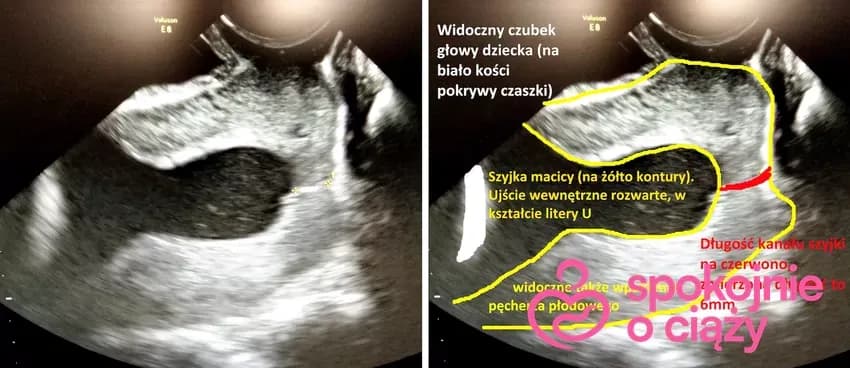

Skrócona szyjka macicy a poród: Kiedy spodziewać się rozwiązania?

Dowiedz się, jak skrócona szyjka macicy wpływa na termin porodu. Poznaj objawy, metody monitorowania i możliwe interwencje medyczne. Ważne informacje dla przyszłych mam.